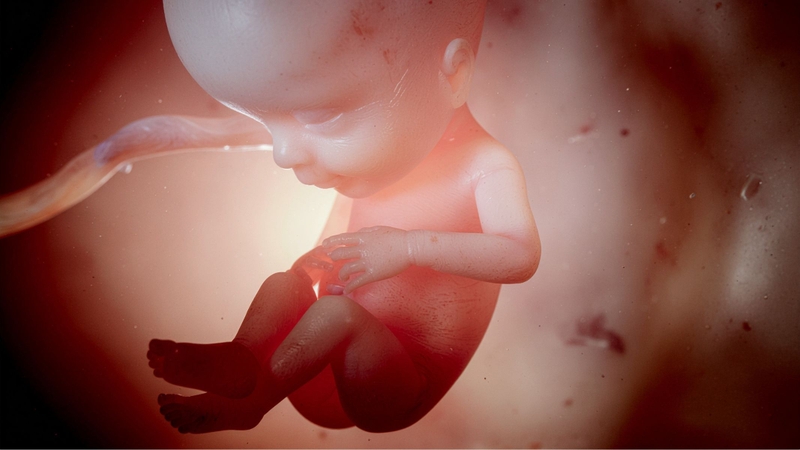

Dây rốn bám mép là tình trạng dây rốn không bám vào trung tâm của bánh nhau mà bám vào mép của bánh nhau. Đây là một dạng bất thường trong thai kỳ có thể ảnh hưởng đến khả năng cung cấp dưỡng chất cho thai nhi. Khi dây rốn bám lệch tâm, không khí và dưỡng chất từ mẹ đến thai nhi có thể bị hạn chế, gây ra nguy cơ thai chậm phát triển hoặc sinh non.

Tình trạng này không chỉ gây ảnh hưởng đến sự phát triển của thai nhi mà còn khiến các bác sĩ phải theo dõi chặt chẽ tình trạng thai kỳ để có phương án xử lý kịp thời khi cần thiết.

Tuy nhiên, do dây rốn bám không vào trung tâm của bánh nhau, quá trình vận chuyển máu, oxy và dưỡng chất từ mẹ đến thai nhi có thể bị giảm. Điều này đặc biệt quan trọng trong những tháng cuối thai kỳ, khi nhu cầu dinh dưỡng của thai nhi gia tăng. Khi lượng máu nuôi thai không được tối ưu, thai nhi có thể gặp phải các vấn đề như: